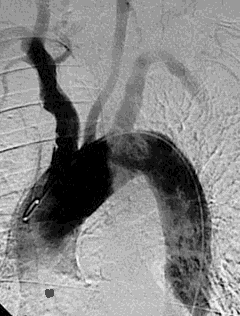

This angiogram demonstrates the aortic arch and great vessels. An embolus from a cardiac valvular vegetation from the left side of the heart can travel out the systemic circulation. Shown here is a septic embolus from infective endocarditis travelling up the left common carotid artery, which could result in a cerebral infarction and/or abscess. |